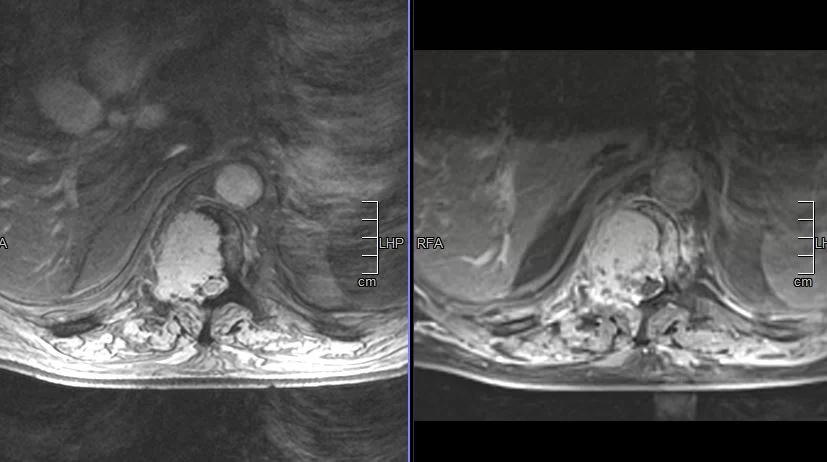

Ο απεικονιστικός έλεγχος με μαγνητική και αξονική τομογραφία της σπονδυλικής στήλης ανέδειξε μάζα κυρίως στο σώμα του 10ου θωρακικού σπονδύλου (Θ10) με περιβρογχισμό και πίεση επί του νωτιαίου μυελού. (Σημειώστε και τη διήθηση του Θ9 σπονδύλου, χωρίς οστεόλυση).